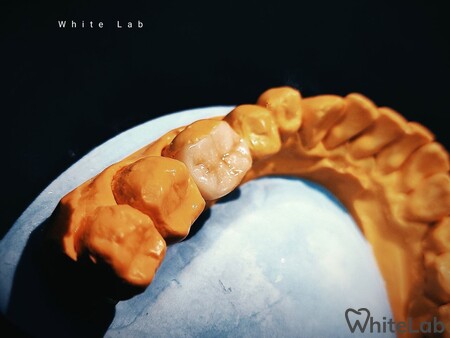

Мы изготавливаем безметалловые виниры и коронки методикой прессования керамики, фрезерование керамики и циркония для создание полной анотомии зуба. Так же используем технику нанесение керамики на рефракторе, при которой слои керамики укладываются послойно, у зуба восстанавливается полная анатомия и он выглядит как натуральный.

Данные методики дают возможность получить естественный, яркий, блестящий вид винирам, коронкам, которые создают самые естественные, реалистичные преобразования улыбки, которые могут быть достигнуты современными технологиями.